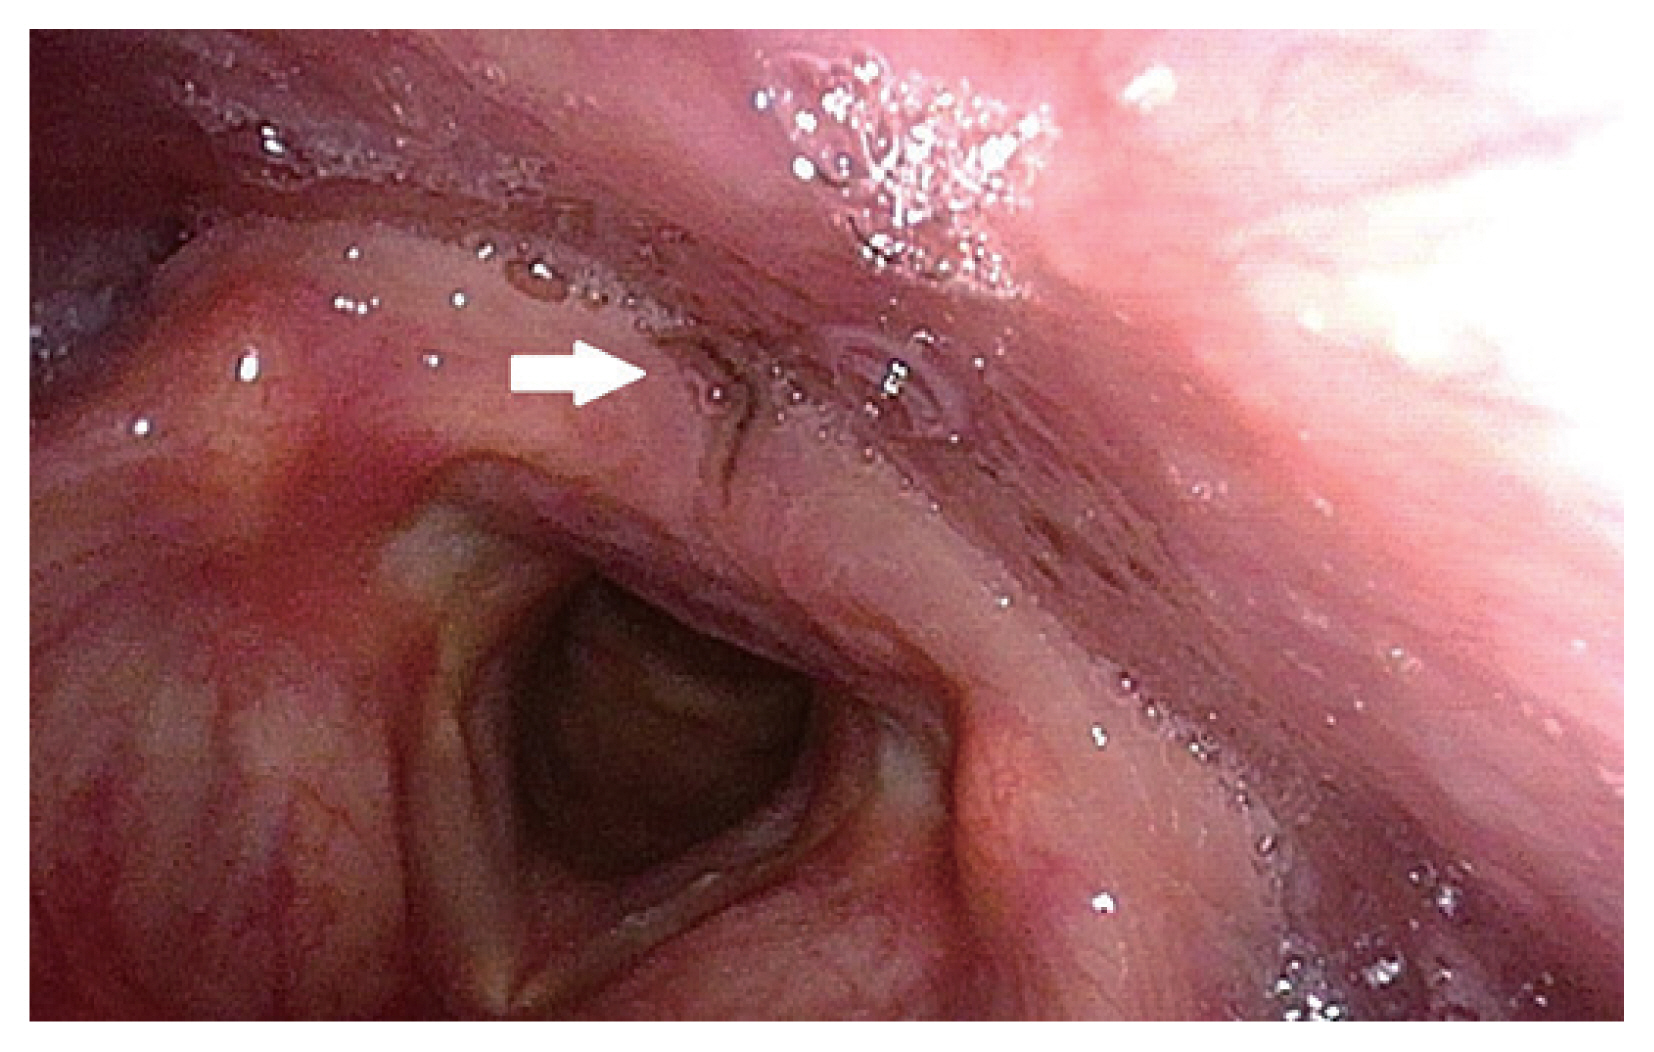

A 46-year old man with no underlying disease was referred to our ENT department from a local clinic for removal of what appeared to be a foreign body (black thread) in pharynx. The patient presented with complaints of foreign body sensation in his throat for the past 2 days and had a history of raw freshwater fish consumption 5 days ago. Close examination under laryngoscopy revealed an approximately 1 cm-sized spontaneously moving organic material located on the posterior pharyngeal wall, just posterior to the interarytenoid mucosa (Fig. 1). The organism was grasped with biopsy forceps under transnasal flexible endoscopy, in which it was cut into 2 pieces during the process; the obtained specimen was sent for pathologic examination and the remnant piece was suctioned and was unable to be retrieved. Pathologic examination with parasitological consultation identified the organism as an adult parasite worm, C. complanatum (Fig. 2). The retrieved portion of the parasite was prepared and stained with hematoxylin and eosin. Morphological examination of the incomplete piece of C. complanatum under light microscopy measured 0.95 mm in length and 0.45 mm in width. The oral sucker which was located anteriorly, measured 0.1 mm long and wide, and the ventral sucker, which was located approximately 0.2 mm caudal to the oral sucker, measured 0.3 mm long and wide. According to measurements from previous reports, the ventral sucker of C. complanatum is located in the anterior third of the body [3]. Considering these morphological characteristics, the total longitudinal length of this parasite could be assumed to be approximately 2.0 mm long. Intestinal caeca were observed bifurcated on both lateral sides of the parasite in symmetry. The portion of the parasite containing reproductive organs was unable to be retrieved. Considering these morphological characteristics and the anatomical site of infection, the parasite was diagnosed as C. complanatum. Follow up endoscopy 1 week after the procedure revealed mild hyperemia of the treated site of mucosa which was completely recovered by the second week. Conservative medical treatment with nonsteroidal anti-inflammatory drug and anti-refluxant drug was provided for 2 weeks, and the foreign body sensation was completely resolved by the last follow-up visit.